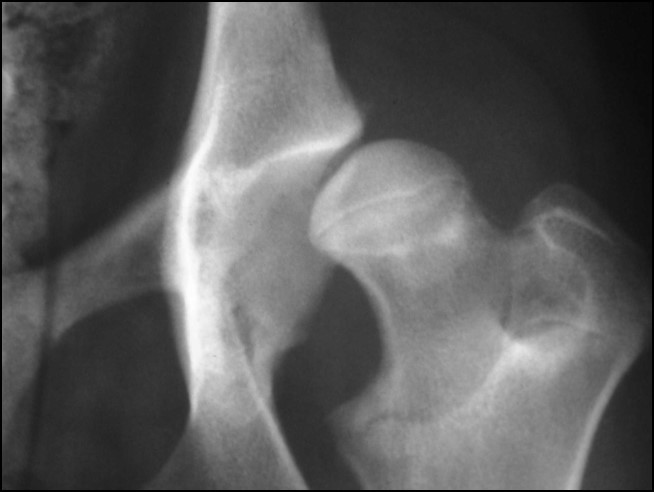

Discuss this radiograph?

Hip dysplasia, cranial acetabulum edge increased opacity